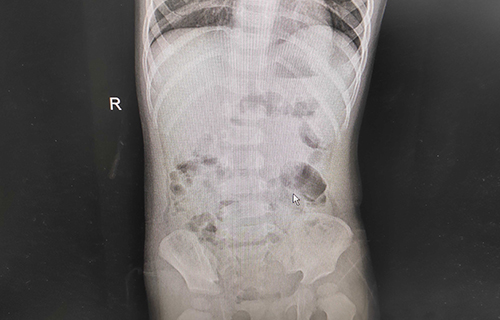

小米妈妈说,孩子发热整整1天,精神萎靡;呕吐2天,平均每天都得吐五六次,呈现非喷射状;腹泻3天,排便呈现水样、蛋花汤样便,尿少。家人急坏了,及时给孩子服用补液盐和双歧三联活菌(益生菌)。在啪啪网 消化内科诊室内,小米依旧精神不振,并伴有轻度脱水。经查体,小米心肺无明显异常,腹部平软,肠鸣音活跃,神经系统正常。综合查体情况,医生初步诊断其为轮状病毒感染导致的小儿肠炎、轻度脱水。在进行肝功能、肾功能、心肌酶、血离子等检查后,医生发现小米的心肌酶数值异常,提示有心肌损害;血钾3.2mmol/L、血糖3.1mmol/L,均低于正常值。在对症治疗后,小米的临床症状得到极大缓解。